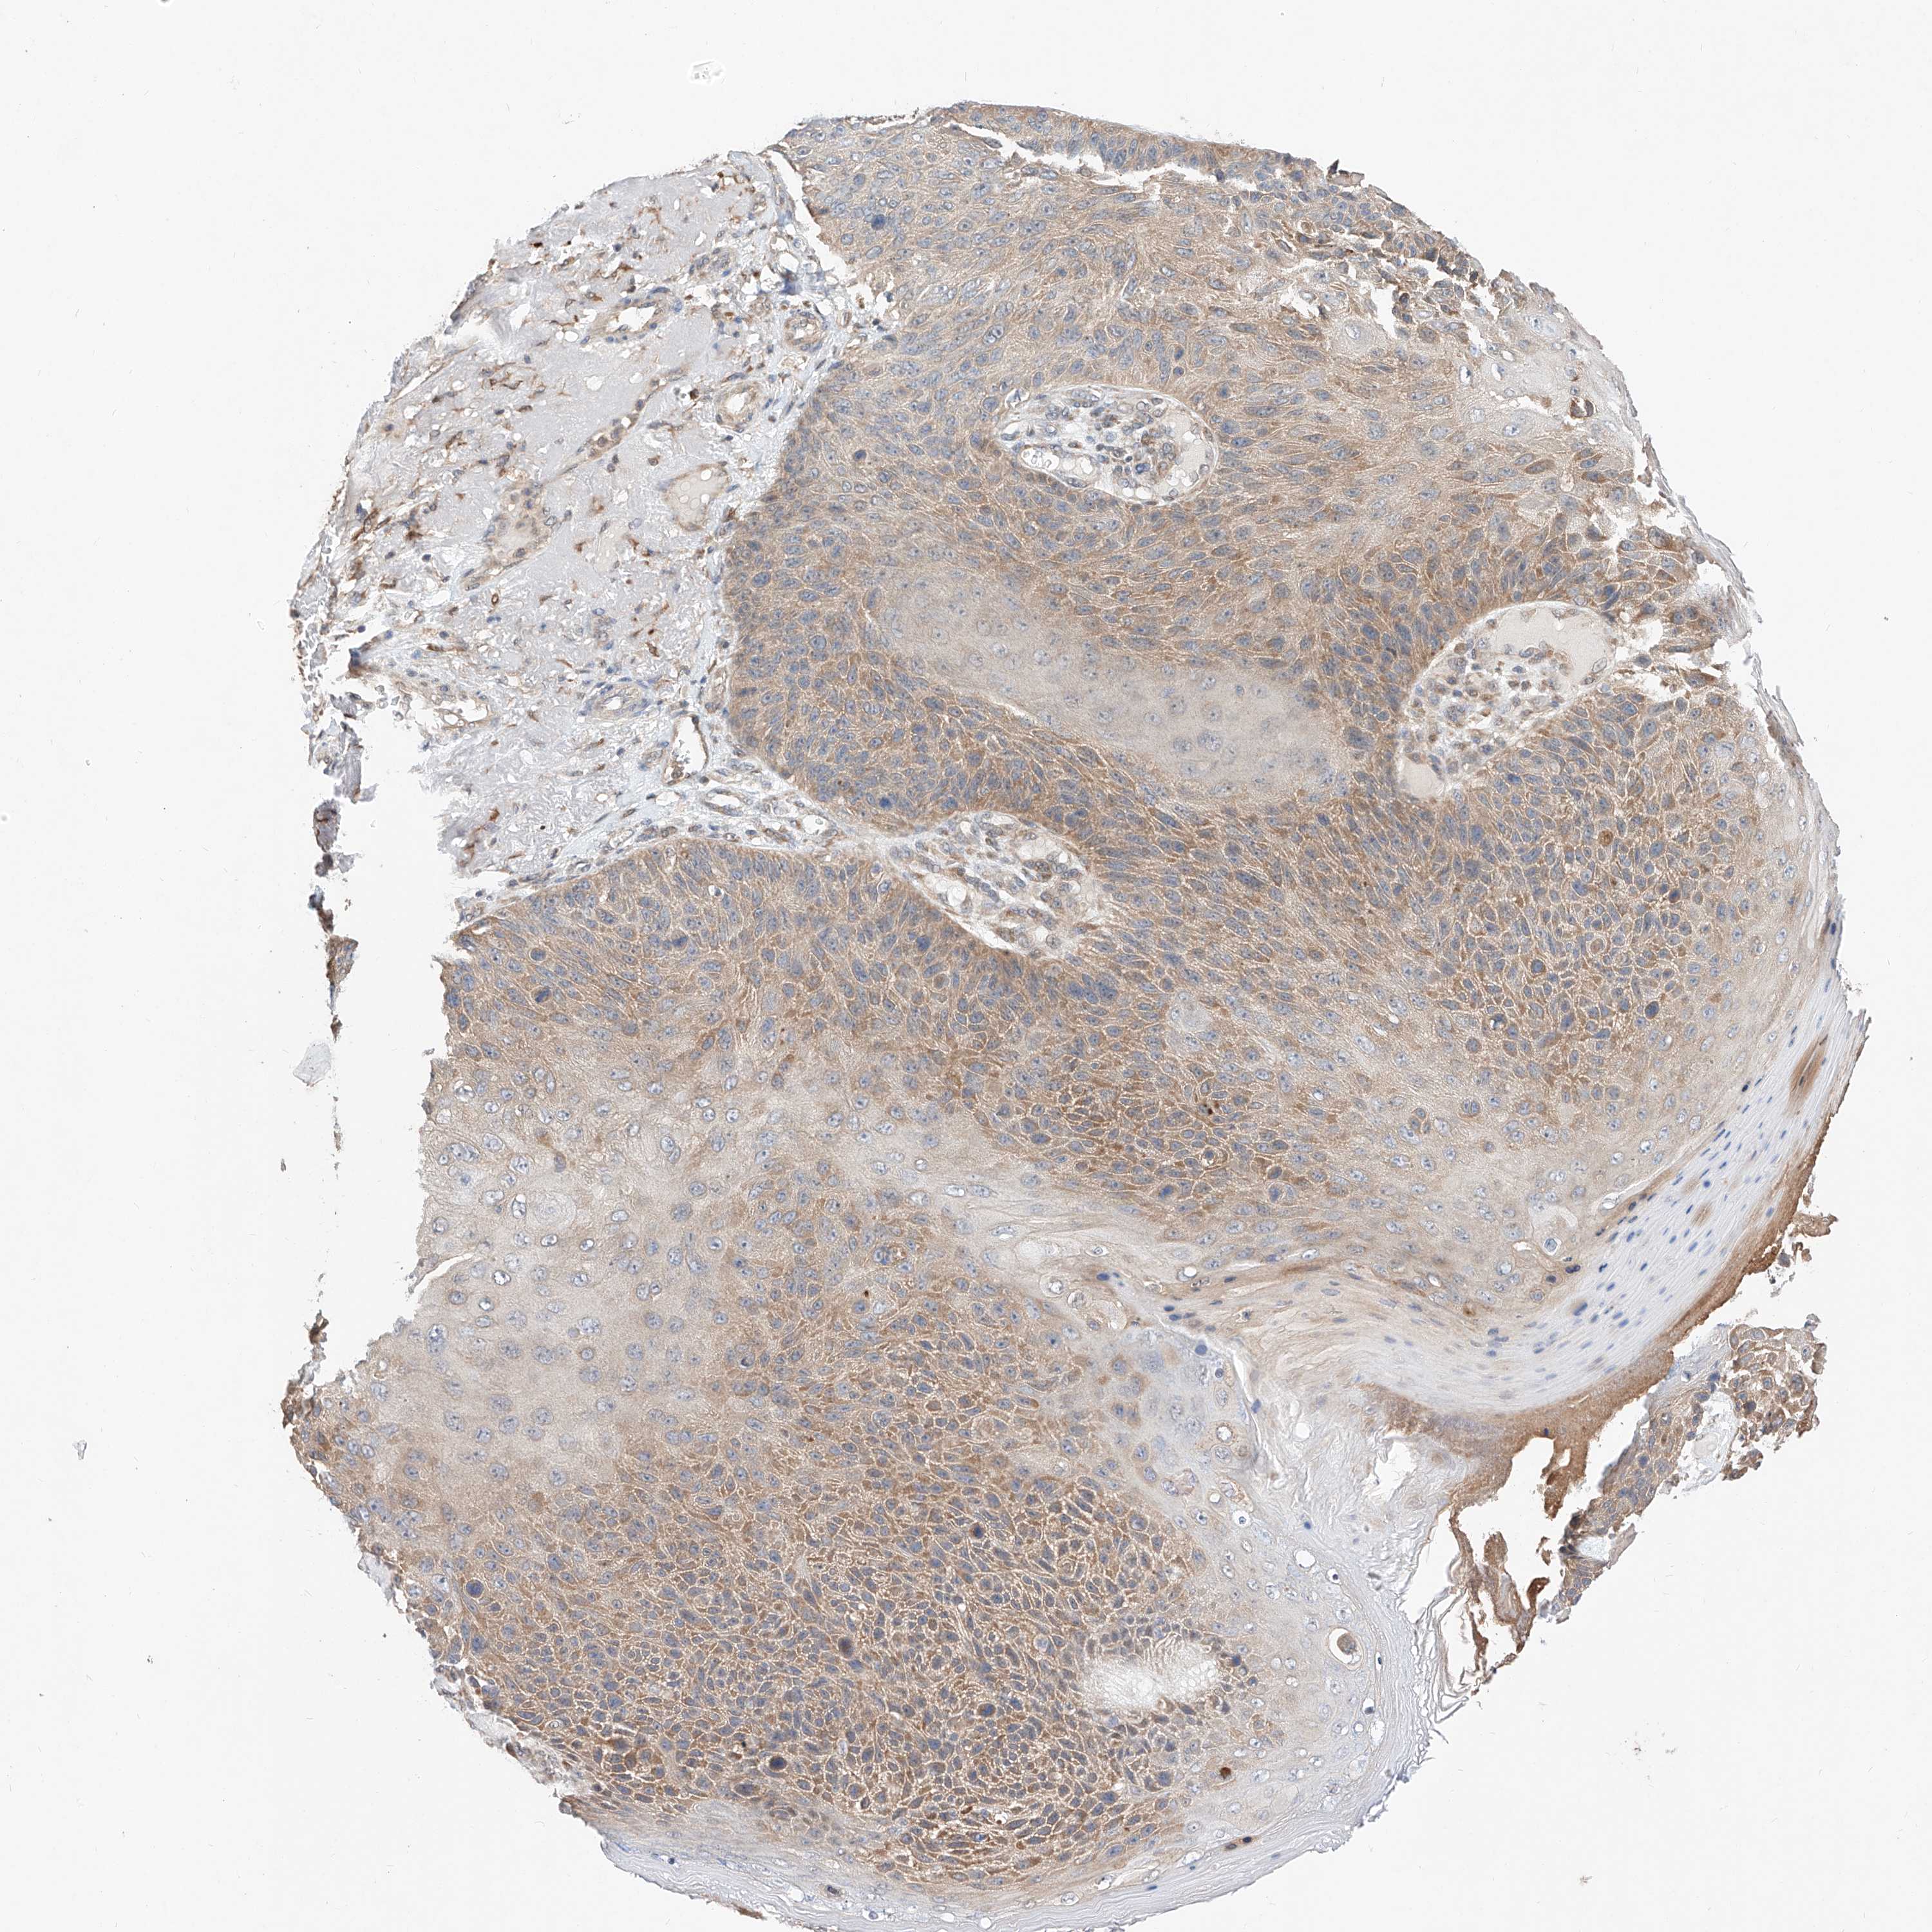

SKIN CANCER - Protein expressioni

A mouse-over function shows sample information and annotation data. Click on an image to view it in a full screen mode. Samples can be filtered based on level of antibody staining by selecting one or several of the following categories: high, medium, low and not detected. The assay and annotation is described here.

Antibody stainingi

Antibody staining in the annotated cell types in the current human tissue is reported as not detected, low, medium, or high, based on conventional immunohistochemistry profiling in selected tissues. This score is based on the combination of the staining intensity and fraction of stained cells.

Each image is clickable and will lead to virtual microscopy that enables deeper exploration of all samples and also displays staining intensity scores, fraction scores and subcellular localization as well as patient and tissue information for each sample.

Antibody HPA006491

Staining

High

Medium

Low

Not detected

Intensity

Strong

Moderate

Weak

Negative

Quantity

>75%

75%-25%

<25%

None

Location

Nuclear

Cytoplasmic/membranous

Cytoplasmic/membranous,nuclear

Squamous cell carcinoma, NOS

Squamous cell carcinoma, metastatic, NOS